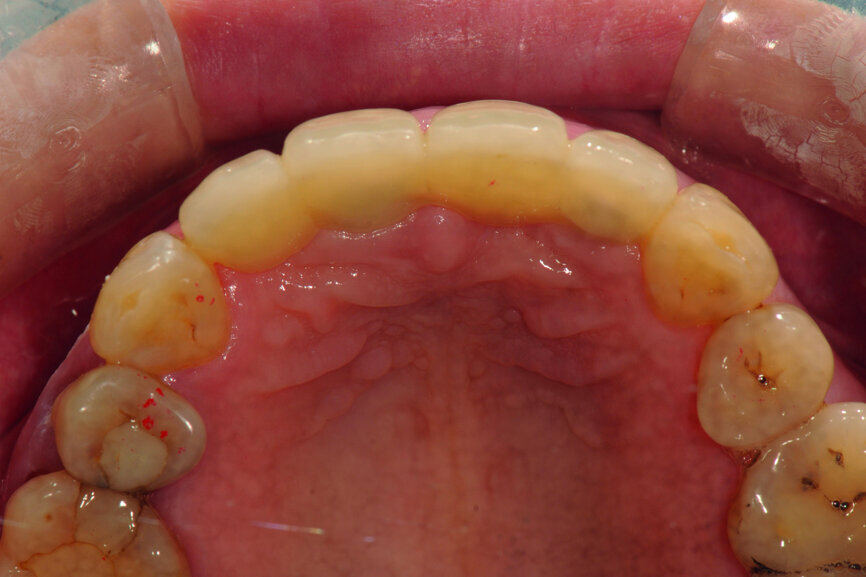

Fig. 2: Pre-op occlusal view of the anterior teeth.

Teeth #12, 21 and 22 were extracted. Tooth #11 underwent early implantation and tooth #22 immediate implantation with GBR (Figs. 5 & 6). After three months of healing, osseointegration had taken place. An implant level impression was taken for fabricating a provisional bridge supported by temporary abutments for teeth #12–22. The technician modified the shape of the artificial gingiva on the model in order to form the proper gingival curve and emergence profile, then finished the provisional bridge, while the dentist modified the gingival shape using an olive-shaped bur intraorally (Figs. 7–18).

Once the aesthetic and functional outcomes had been confirmed, the anterior guidance of the provisional restoration was recorded on an articulator (Artex, Amann Girrbach) and its individual incisal guide table (Figs. 24–27). Next, the emergence profile of the provisional restoration was transferred and the cast model was made and mounted on the articulator (Figs. 28–33).